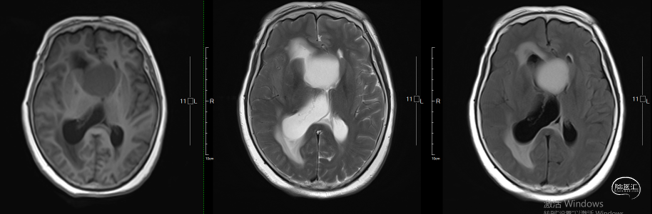

术后影像学

头部MRI提示:影像学全切,脑积水得到明显好转,实性部分未见显影,垂体组织保留良好。